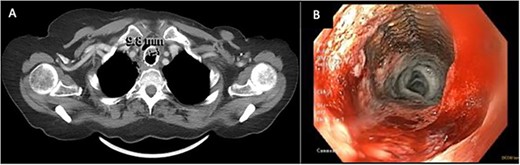

(A) CT image from January 2021 showing severe narrowing of the lumen of the esophagus proximal to the stent. (B) EDG from February2021 showing response to balloon dilation of a stricture proximal to the indwelling stent.

Palliative supports for the patient were arranged. CT scan at this time (January 2021, Fig. 2A) showed severe luminal narrowing of the esophagus proximal to the stent. The patient initially declined a feeding gastrostomy tube to avoid further aspiration. Instead, repeat EGD with balloon dilatations were performed to relieve dysphagia (Fig. 2B). TEF was still not detected on bronchoscopy or on barium esophagogram. The patient continued to have recurrent pulmonary infections treated with oral antibiotics. In April 2021, a percutaneous endoscopic gastrostomy tube was inserted to facilitate enteral nutrition and minimize aspiration.